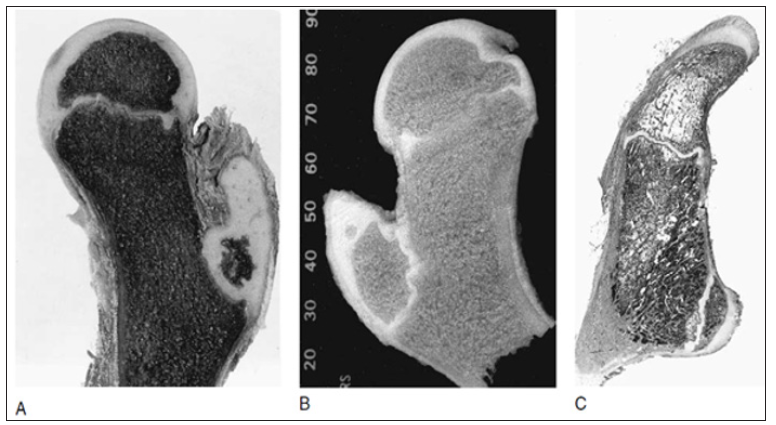

Secondary ossification usually begins in the capital femur by 4-6 months postnatally (range 2-10 months). This process is a centrally located sphere of ossification that expands centrifugally, eventually conforming to the hemispheric shape of the articular surface by the time the child is 6-8 years old and forming a discrete subchondral plate that follows the capital femoral physeal contour [3]. Throughout most of the development the capital femoral and trochanteric epiphyses have a cartilaginous continuity along the posterior and superior portions of the femoral neck (Figure 2). Although this region gradually thins as the child grows, it is essential for the normal latitudinal growth of the femoral neck and, in part, the normal decrease in anteversion (Figure 2).

Figure 2: (A) Progressive proximal femoral development. A segment of physeal cartilage (arrows) is present along the posterosuperior femoral neck throughout most of development. It is necessary for widening of the femoral neck and posteriorly directed growth of the femoral neck to spontaneously decrease the amount of anteversion. (B) Transverse section through the proximal femur showing the capital femoral epiphysis and the posterior cartilaginous continuity (arrows) with the unossified greater trochanter (Ogden JA, 1983).

Figure 3: (A) Development of trochanteric ossification in an 8-year-old child, showing the irregular margins of secondary ossification and the extensive cartilaginous nature of the trochanteric epiphysis, especially proximally at the tip. (B) Later stage (12years) showing an accessory (tertiary) ossification center. (C)Histologic section through the greater and lesser trochanters in a 15-year-old boy (Ogden JA, 1983).

Ossification begins in the greater trochanter at 5-7 years (Figure 3) and is initially present directly above the trochanteric physis. With further development, ossification proceeds cephalad into the remainder of the epiphysis. Epiphysiodesis of the greater trochanter occurs at 14-16 years (usually later than in the capital femoral physis). The lesser trochanter does not usually ossify until adolescence (Figure 3). Fusion occurs between 15 and 19 years. This region is subject to high tensile stresses from the attached iliopsoas tendon and represents a traction apophysis. Overgrowth may occur owing to chronic stress, as with cerebral palsy.